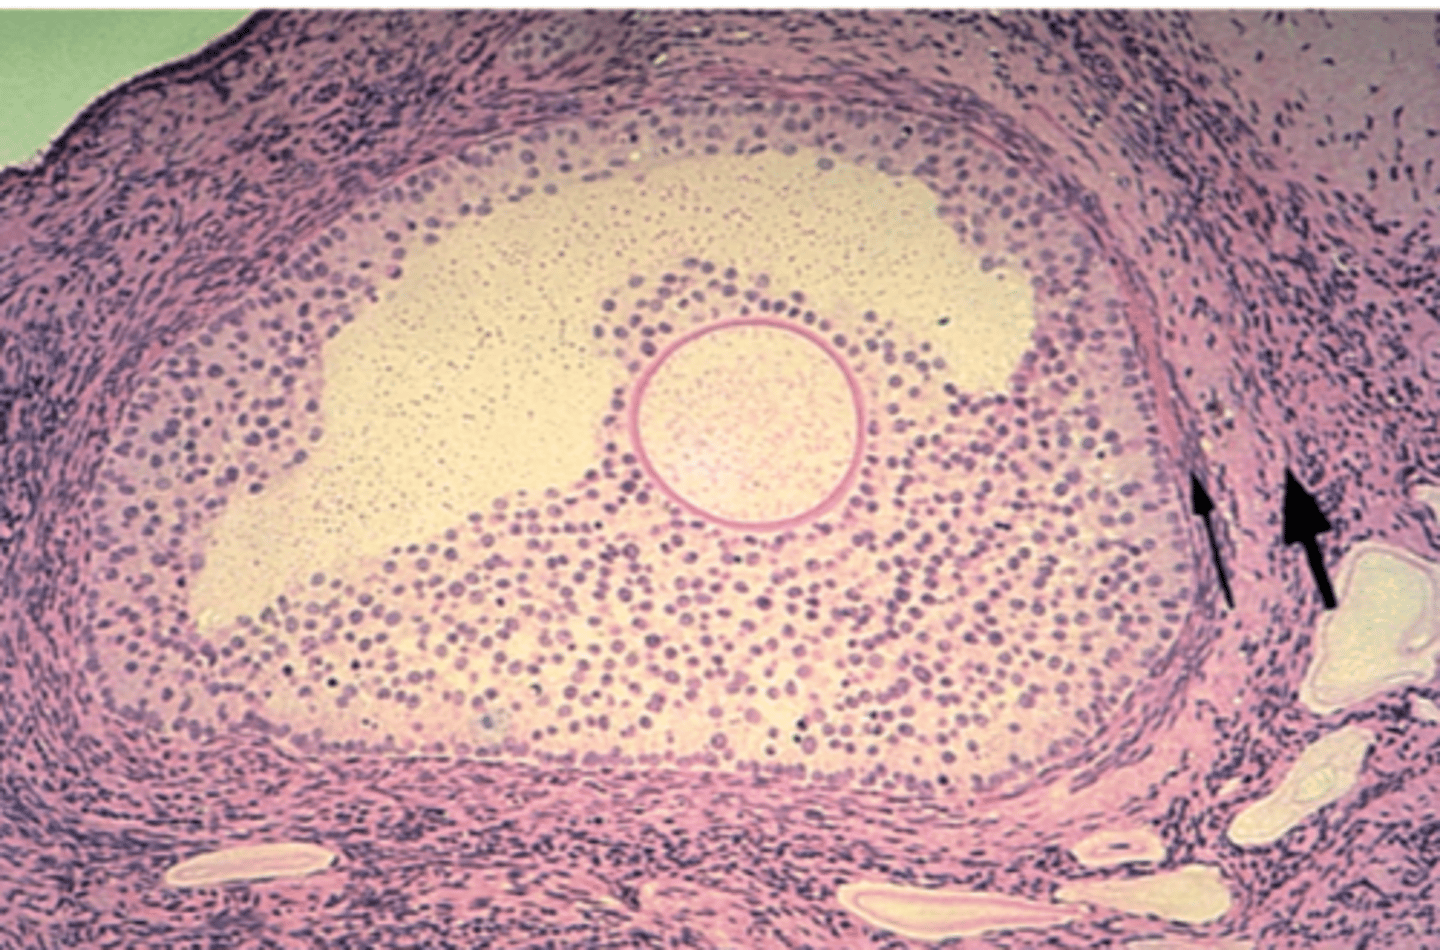

testis

What is this?

testis

What is this?